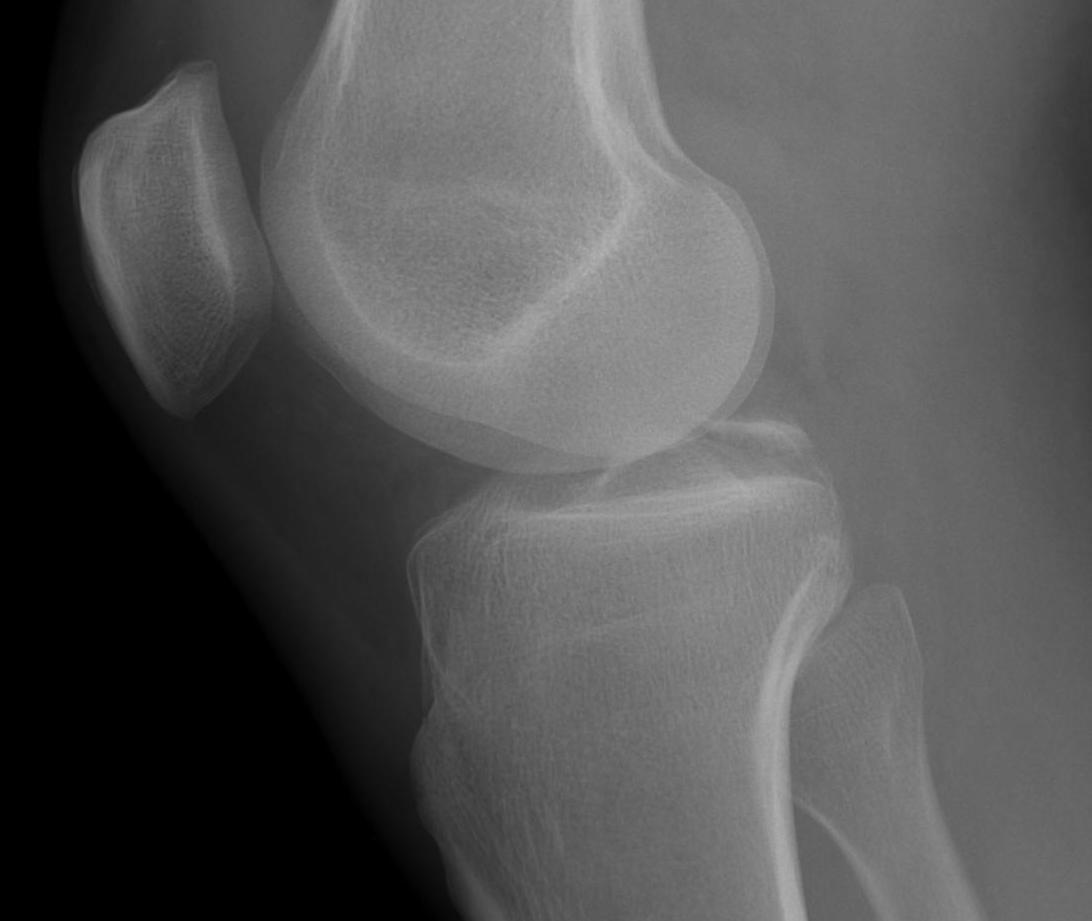

Bony Avulsion

Chronic bony avulsion PCL

Posterior subluxation of tibia

Grade 3 PCL disruption - posterior tibia subluxed behind posterior aspect femoral condyles